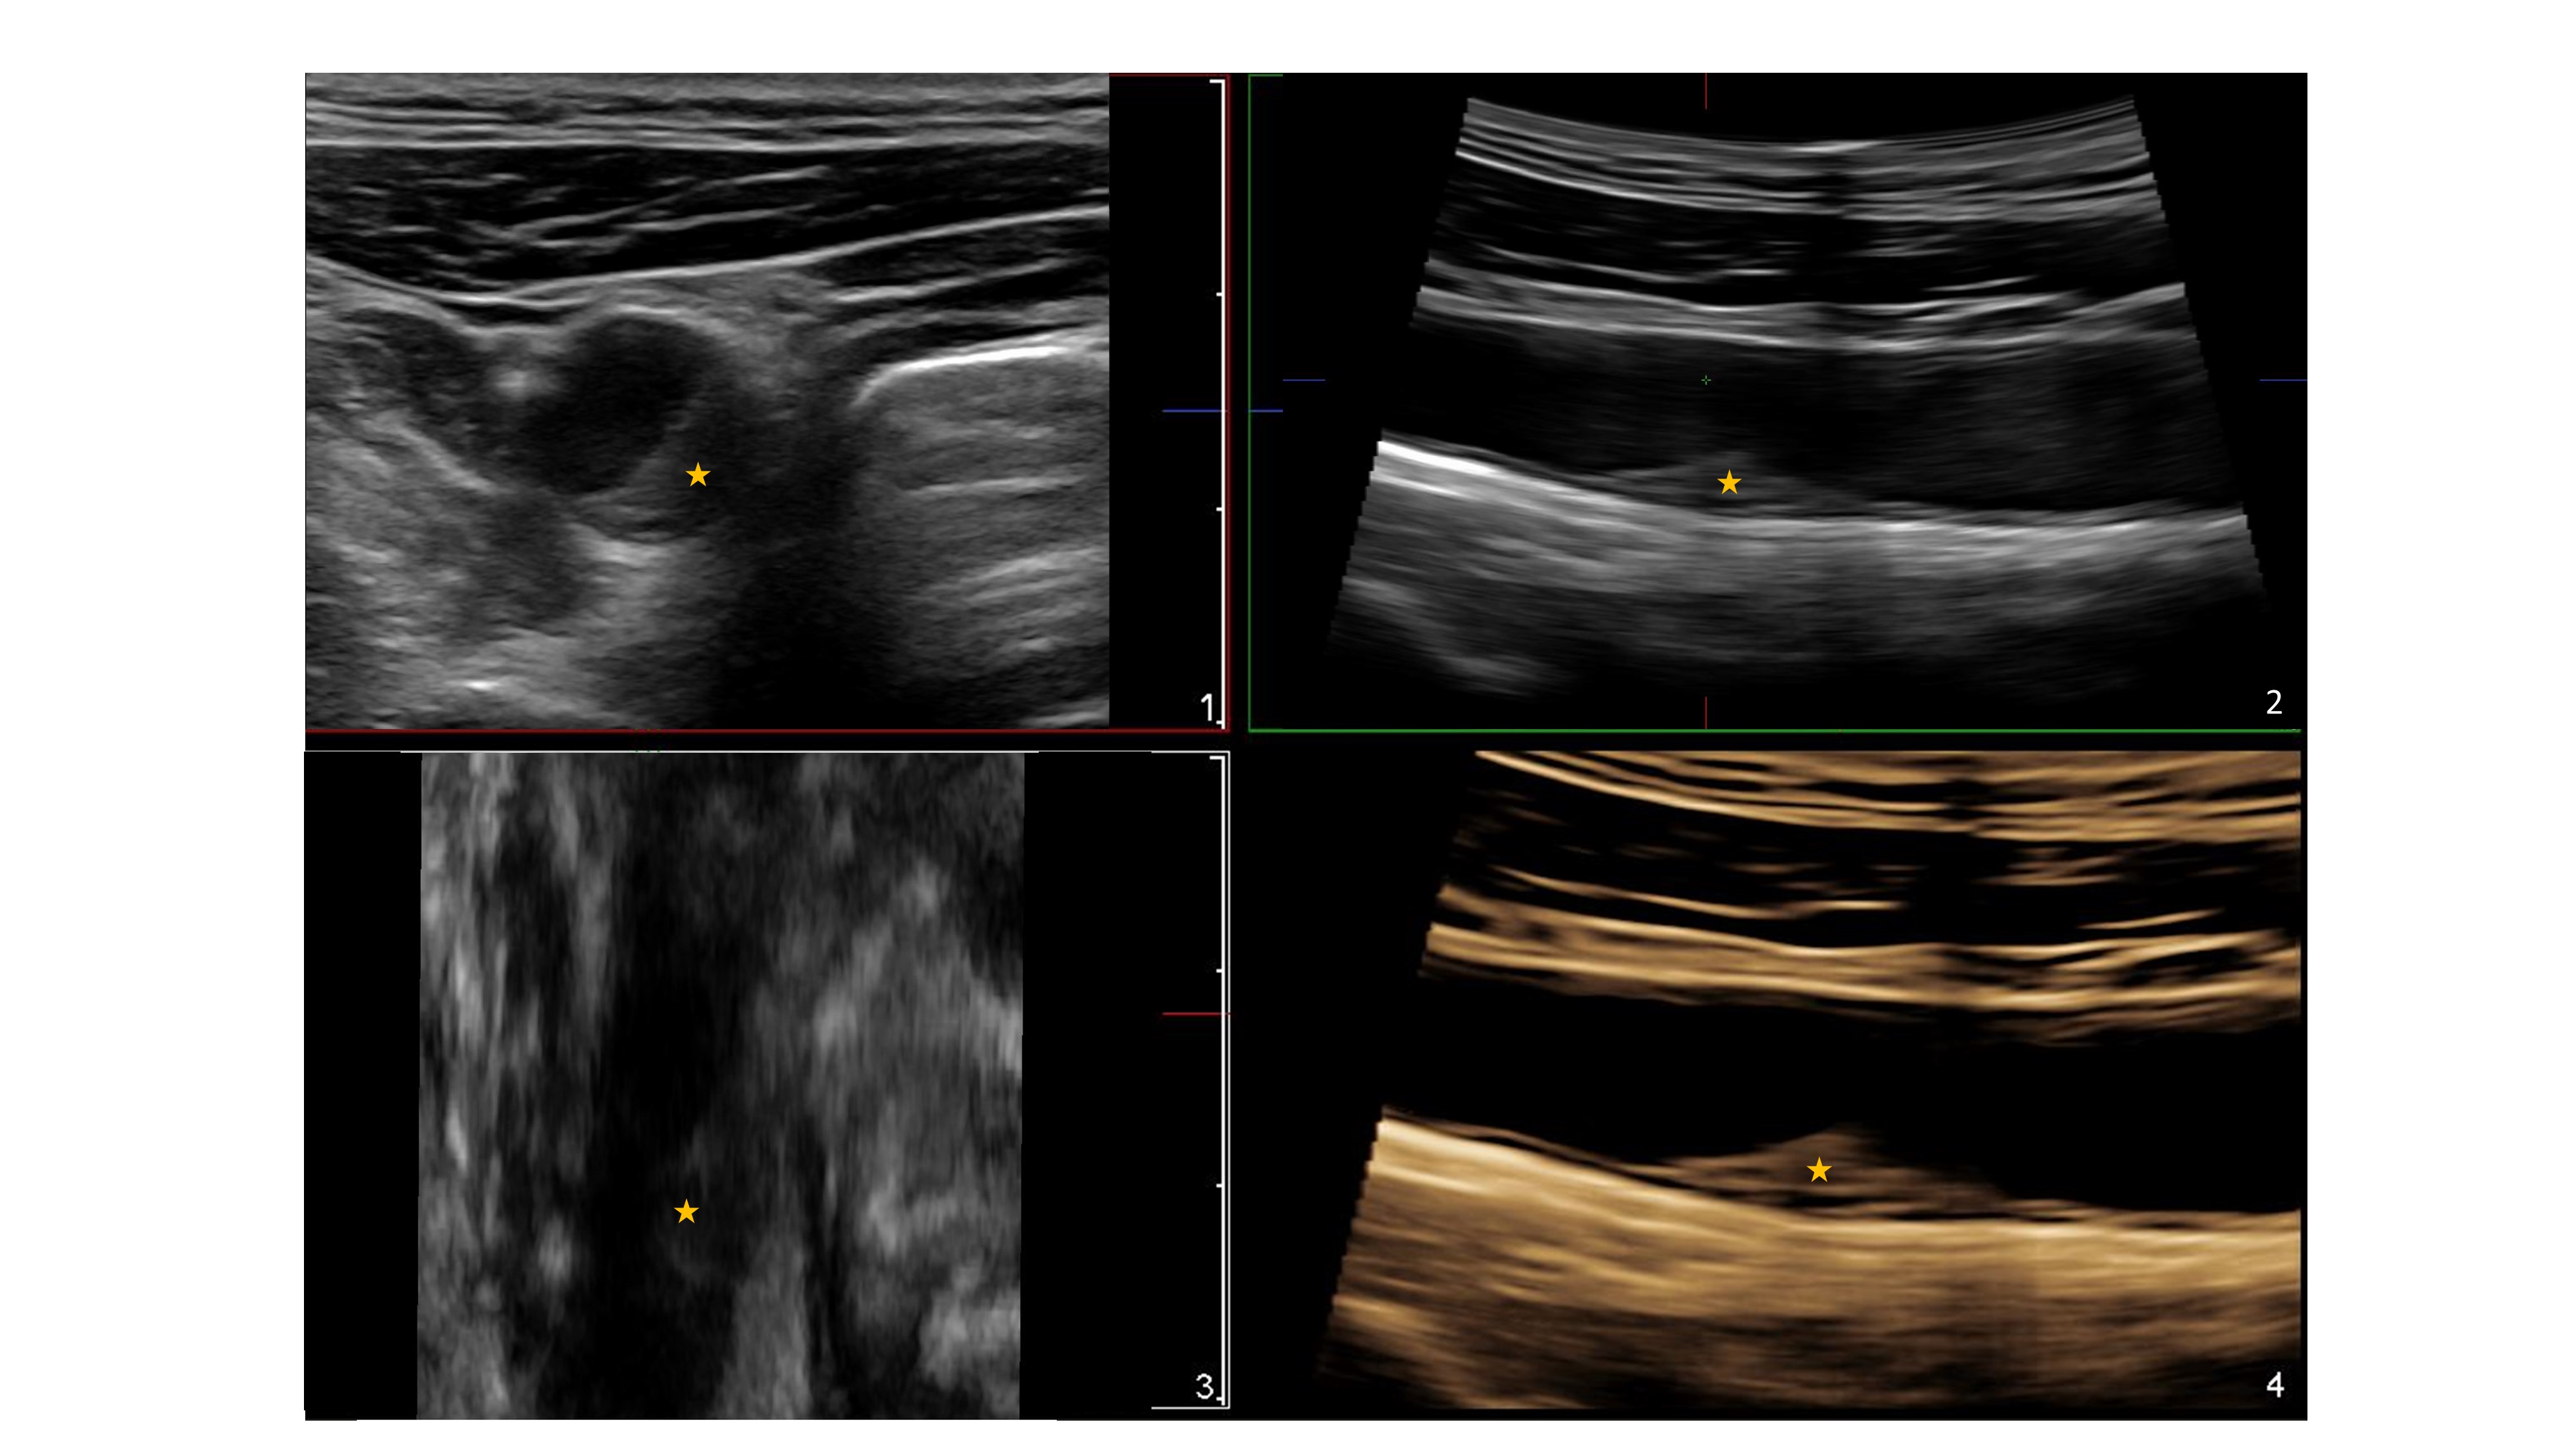

*Imagen:

Se muestra con asterisco la presencia de una placa de aterosclerosis avanzada en la carótida común detectada por la técnica de ecografía 3D que no llega a ocasionar una obstrucción significativa de la luz del vaso (es <50%). Se puede comprobar con precisión su extensión en las 3 dimensiones del espacio lo que nos permite detectar cambios en su volumen para determinar si existe un avance de la enfermedad.